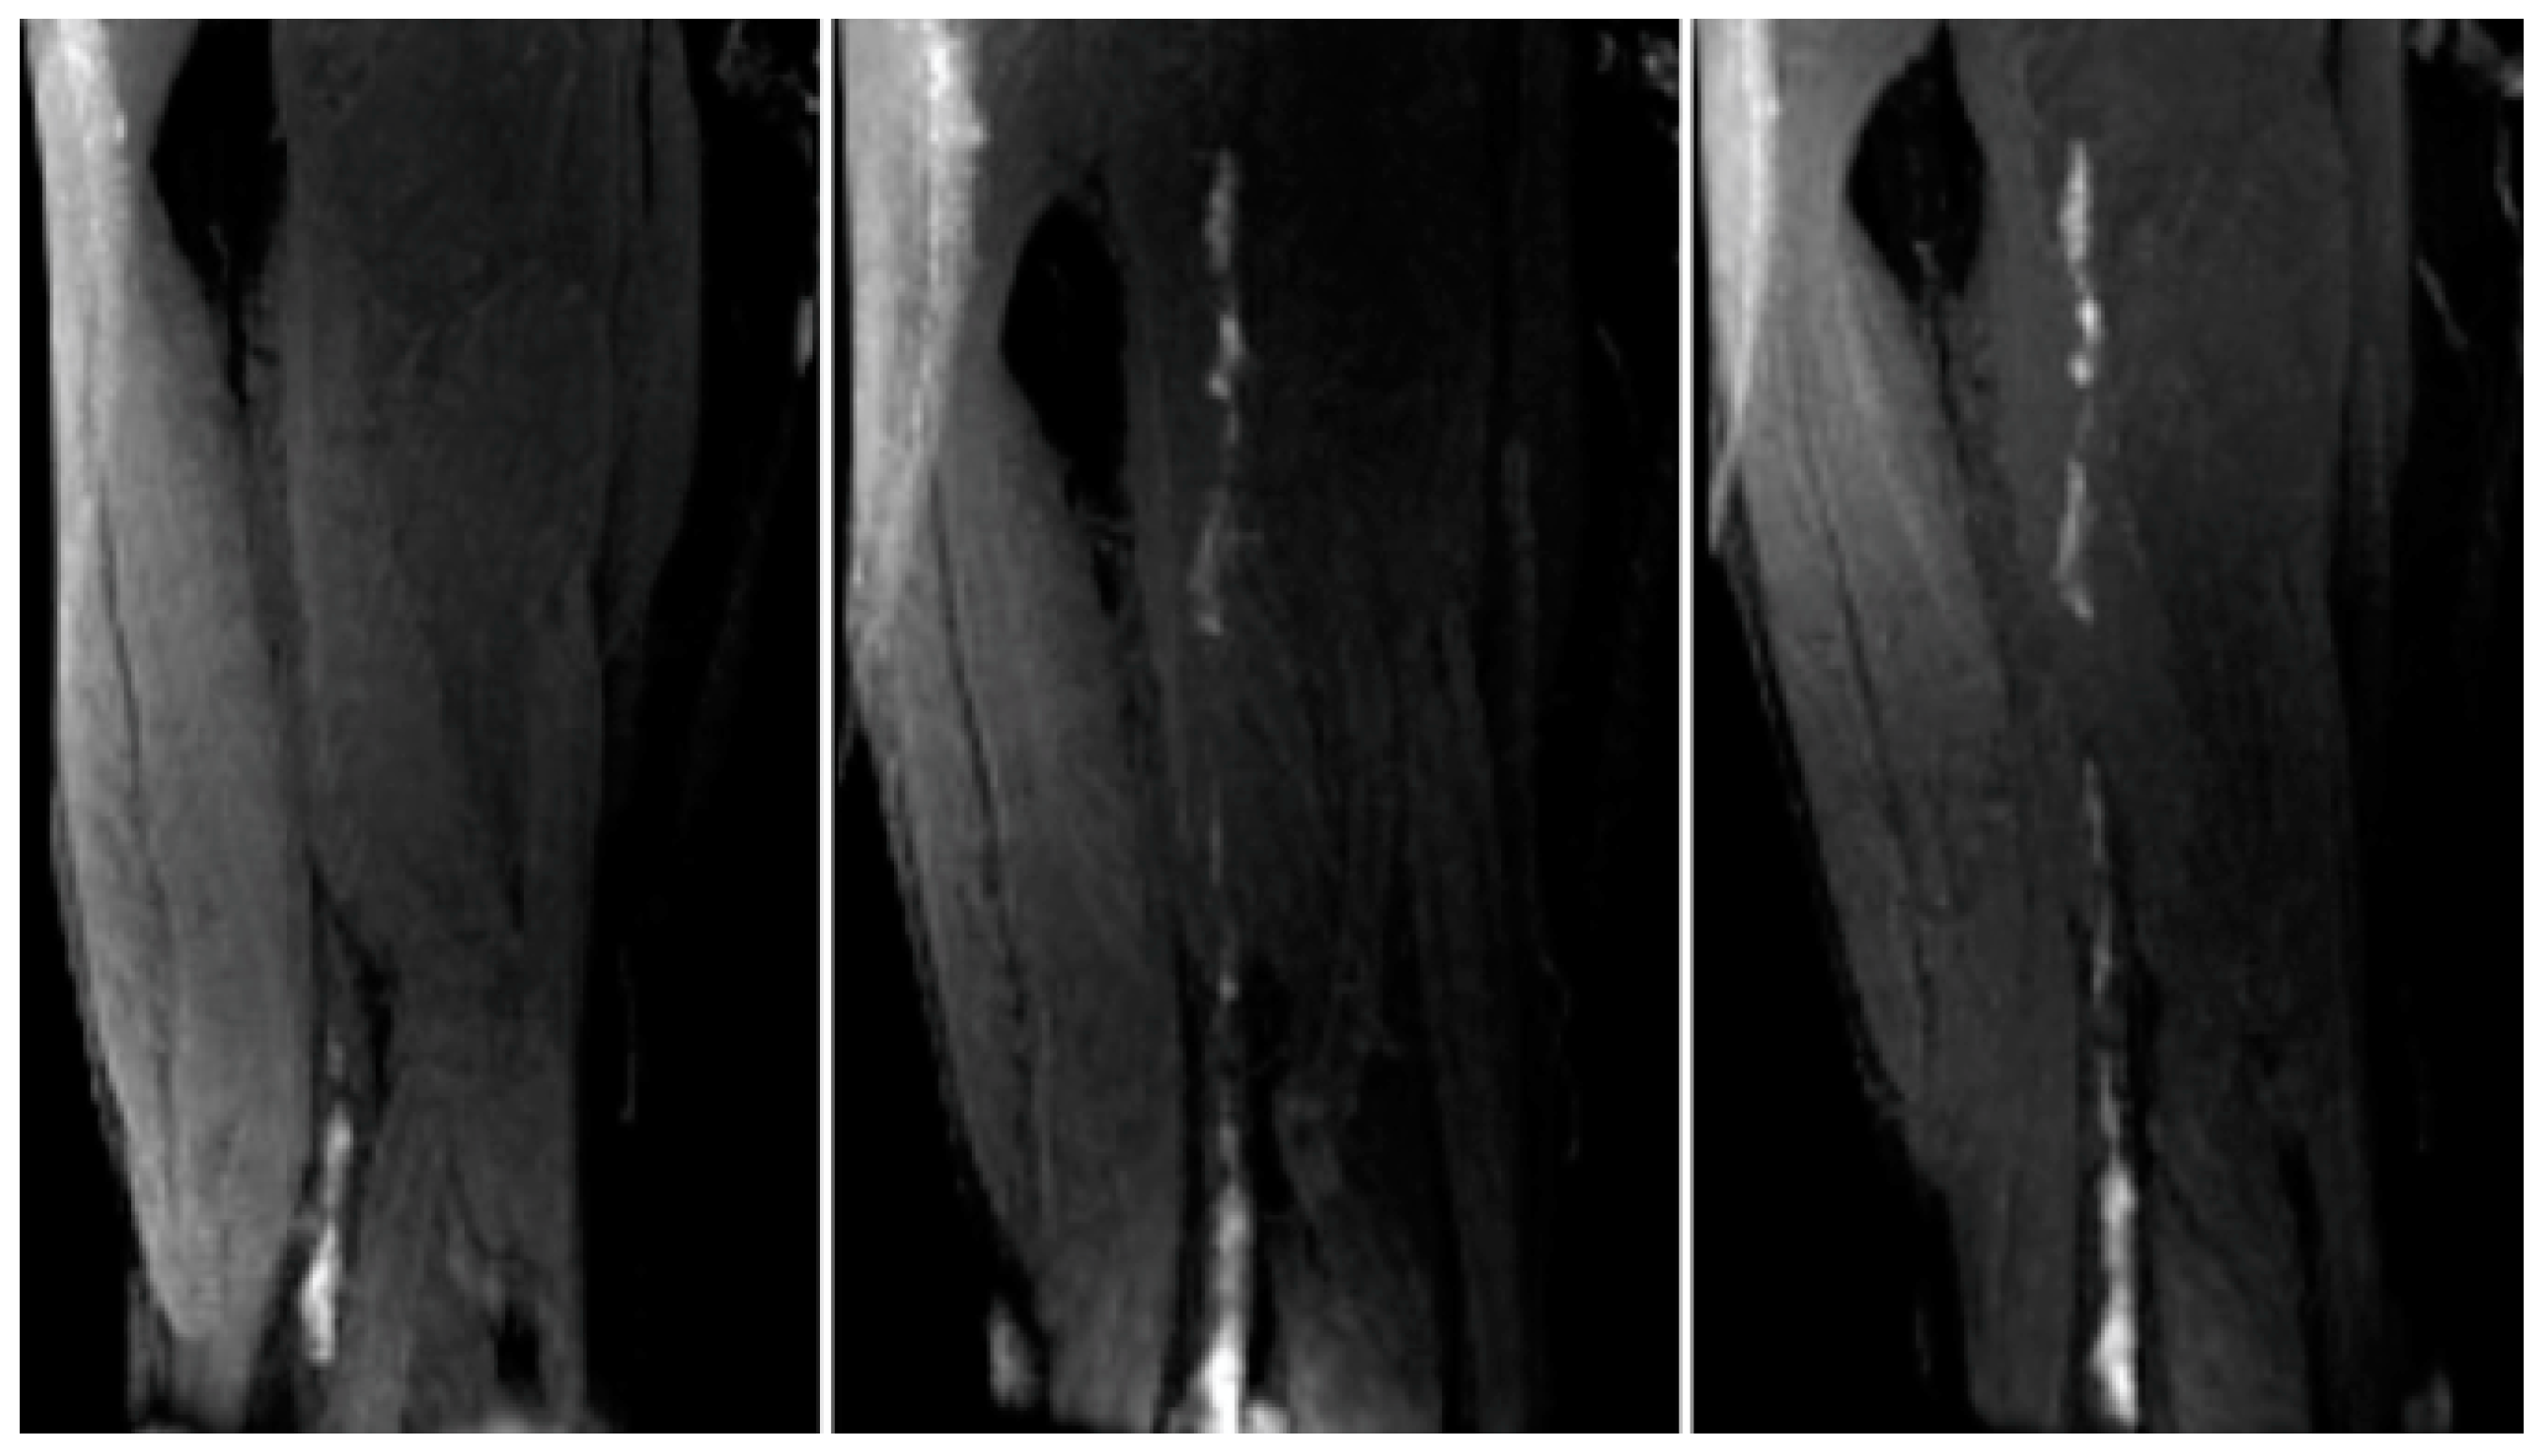

- Saha, P.; Andia, M.E.; Modarai, B.; Blume, U.; Humphries, J.; Patel, A.S.; Phinikaridou, A.; Evans, C.E.; Mattock, K.; Grover, S.P.; et al. Magnetic Resonance T 1Relaxation Time of Venous Thrombus Is Determined by Iron Processing and Predicts Susceptibility to Lysis. Circulation 2013, 128, 729–736. [Google Scholar] [CrossRef]

- Phinikaridou, A.; Andia, M.E.; Saha, P.; Modarai, B.; Smith, A.; Botnar, R.M. In vivo magnetization transfer and diffusion-weighted magnetic resonance imaging detects thrombus composition in a mouse model of deep vein thrombosis. Circ. Cardiovasc. Imaging 2013, 6, 433–440. [Google Scholar] [CrossRef]

- Wu, G.; Morelli, J.; Xiong, Y.; Liu, X.; Li, X. Diffusion weighted cardiovascular magnetic resonance imaging for discriminating acute from non-acute deep venous Thrombus. J. Cardiovasc. Magn. Reson. 2019, 21, 667. [Google Scholar] [CrossRef]